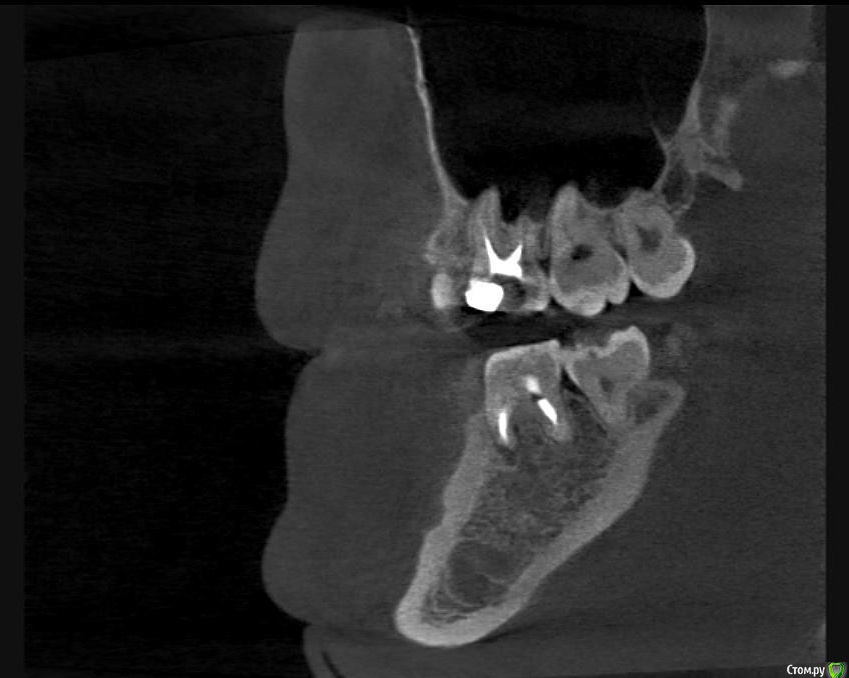

Л Ю С Я Опубликовано 10 января, 2014 Поделиться Опубликовано 10 января, 2014 .Новый кейс-совсем свежий пока без долгосрочного результата.Пациентка попала случайно удаляла зуб 28 и хирург сделал ОПТГ,где стали видны обширные периапикальные процессы в области 37 47.Побывав у меня на консультации и услышав план лечения и стоимость,пациентка решила видимо полечить подешевле.,побывав на консультациях в нескольких клиниках и в итоге даже попала к главному стоматологу нашей области. Все ей сказали что удаление онли. Вернулась,-засада была в том что план я писал исходя из ОТПГ не сделав прицел(виноват),сделав прицел понимаю что все сложнее чем я думал-ну что же тем интереснее.Переписав план лечения и подняв ценник на 40%(пациентке не оставалась выбора),начали лечение.1-посещение-ревизия пломбы.понимаю что кто то до меня с маниакальным упорством пытался запломбировать мезиальный язычный канал каналонаполнителями. Убрал два фрагмента из верхней трети мезиального язычного.2-посещение еще фрагмент из мез язычного плюс немного с дистальными поработал(их оказалось два сплит в верхней трети)3-визит обошел фрагмент в мезиальном щечном и доработал остальные каналы.4-визит -паковка.На предпоследнем снимке видны поры-допаковал(просто на финальном не очень видно)Класс! Ждем рекол через 6 месяцев. Паковка чем? Сквирт? Ссылка на комментарий

Hans85 Опубликовано 14 января, 2015 Автор Поделиться Опубликовано 14 января, 2015 Полагаю на КТ будет не такая уж радужная картинка...Чем завершено лечение? Коронка?Наконец то пациент пришел на коронку.Вот и Кт ,да заживление не 100% ,но все же . 3 Ссылка на комментарий